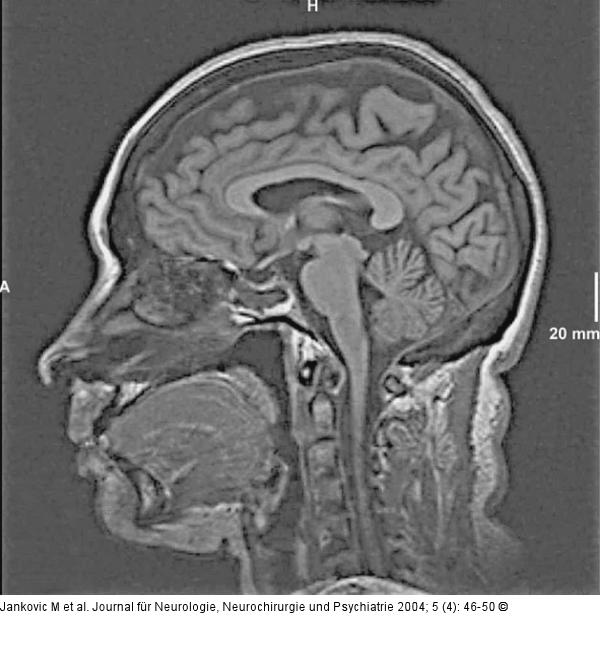

Abbildung 1: Epileptische Anfälle - intrathekale Fluoreszeinapplikation Die t1-gewichtete MRT des Gehirns in median-sagittaler Schnittführung zeigt den Operationsdefekt nach transsphenoidaler Hypophysenadenomoperation im Bereich der Keilbeinhöhle. |

Die t1-gewichtete MRT des Gehirns in median-sagittaler Schnittführung zeigt den Operationsdefekt nach transsphenoidaler Hypophysenadenomoperation im Bereich der Keilbeinhöhle. |